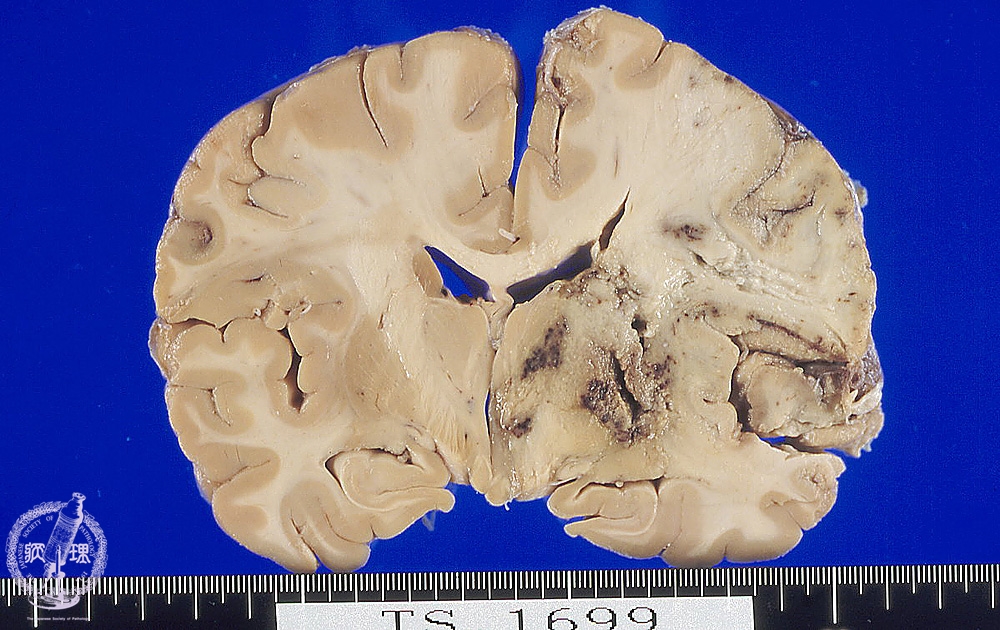

Macroscopic findings: Extensive infarction was detected from the right cerebral cortex to the basal ganglia. Infarcted region appeared pale and swollen and the cortex was indistinguishable from the medulla. Dark brown colored hemorrhage was also appreciated in the basal ganglia.

Click the image to see the enlarged image.